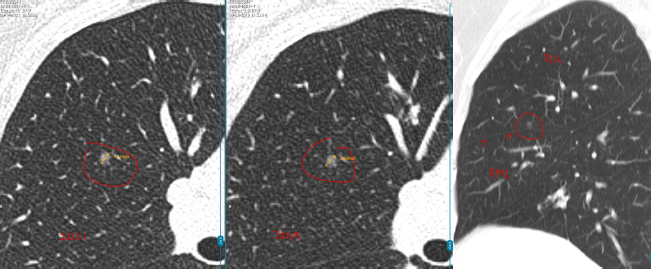

数年前,孙女士(化名)在一次体检中意外查出双肺多发结节:

左肺下叶:2枚实性结节,约5mm、3mm

右肺上叶:1枚磨玻璃结节,约4mm

每年复查,她都紧张得睡不着。好在3个结节都一直很“老实”,没变大。可四年后的一次CT复查,让她的心又提了起来:

左肺结节无变化,但右肺的4mm结节密度增高了,还又新添了一颗3mm的磨玻璃结节。

L教授详细查看了孙女士4年来的全部影像资料后,给出的结论让她长舒了一口气。

教授指出,右肺那颗4mm的磨玻璃结节虽然密度略有增加,但变化非常小,还不足以判断为恶化。

而左肺的两枚实性结节稳定了三年多,良性可能性超过99%。另外舌叶可见线状影,较前稳定,符合炎性、瘢痕特征。

至于新出现的那颗3mm磨玻璃结节,教授认为它也很“温和”,更像是一种暂时的炎性反应,有可能过段时间就自行消失了。

“这些结节都太小,目前还不到该切的程度,继续观察很安全。”L教授说。他建议孙女士每年复查一次CT,不需要手术、不用活检。